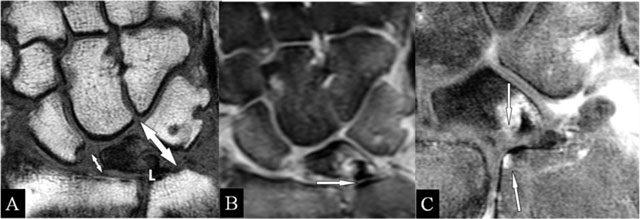

Lunar abutment

Avascular necrosis – probably due to chronic microtraumata – with deformation starts at the radial side [15]. Due to the height loss, the ulnar side approaches the ulna (reversed situation of ulnar abutment) (Figure 7A). The normal ulnar variance and the late appearance of sclerotic borders may be observed on radiographs. Early BMO and TFCC lesions call for MRI (Figure 7B and C).

Figure 7

Lunar abutment. (A) Coronal SE T1-WI; (B) Coronal SE PD-WI FS; and (C) Coronal SE T1-WI FS with gadolinium. (A) Due to loss of height at the radial side, the ulnar side of the lunate bone (L) approaches the ulnar head. (B) Sclerotic borders at the contact zones (arrow), oedema at the ulnar corner of the lunate bone and TFCC tear. (C) Contrast enhancement in the zones of the kissing marrow oedema.

Scapholunar abutment

On radiographs (Figure 8A), a widened joint space (≥3 mm) [16] in rest or under stress (Schneck view) may be observed. MRI may show the ligamentous tear (Figure 8B) and the juxta-articular band shaped BMO (Figure 8C).

Figure 8

Scapholunar and lunotriquetral abutment. (A) PA plain radiograph; (B) Coronal SE PD-WI FS; (C) Coronal SE T2-WI FS; (D) Coronal 2D-GRE; (E) Coronal SE T2-WI FS; and (F) PA plain radiograph. (A) Widening of the scapholunate joint space on a Schneck I view. (B) Tear of the scapholunate ligament. (C) Juxta-articular subchondral band shaped marrow oedema. (D) Tear of the lunotriquetral ligament. (E) Juxta-articular band shaped kissing marrow oedema. (F) Massive deformation at the triquetral bone (other patient).

Lunotriquetral abutment

MRI may also show this ligamentous tear (Figure 8D) and the band-shaped BMO (Figure 8E). Eventual concurrent extrinsic ligamentous lesions should be looked for, as it is questionable if this solitary lesion results in abnormal mobility [17]. Due to chronic impaction, massive deformation may appear on radiographs (Figure 8F).